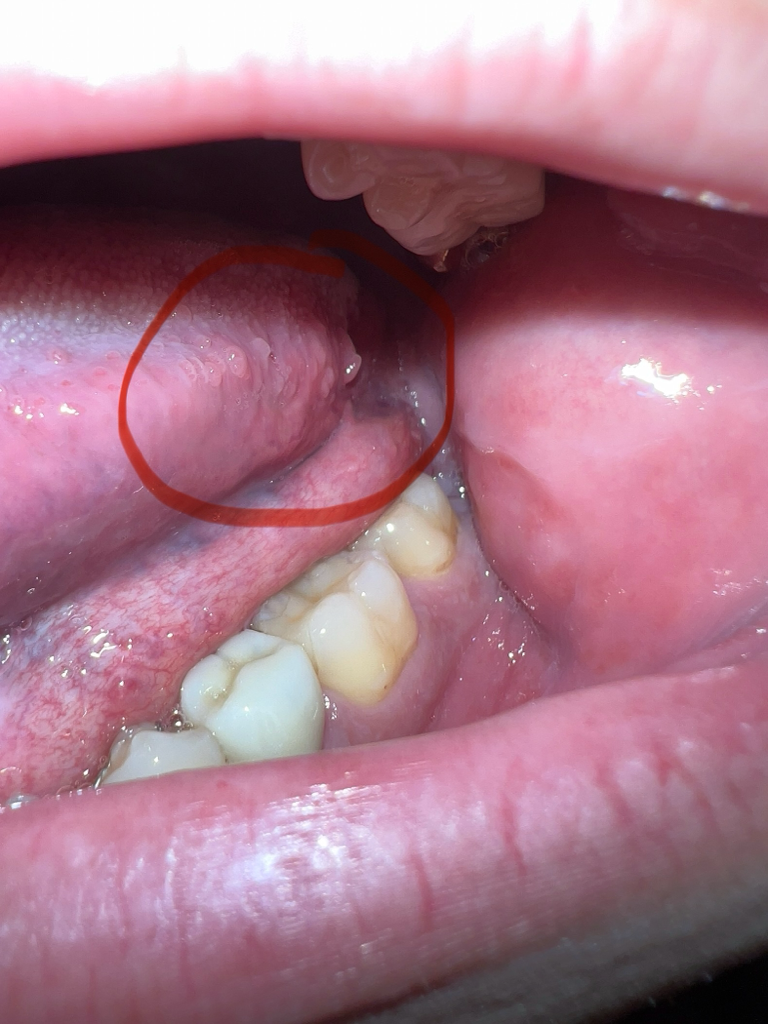

혀안에 아픔은 없고 뭔가 수포같아보이는데 수포는 아닌게 있네요

혀안쪽에 수포처럼 보여서 만져보니 덜렁덜렁 거리는데 이것도 구내염 혹은 질병에 의한걸까요? 아니면 혀쪽에 원래 이런것도 생기나요

혀안에 정상적으로 생길 수 있는 병변이며 특별히 통증이 없거나, 크기에 변화가 없다면 경과관찰이 가능하실 것 같습니다.